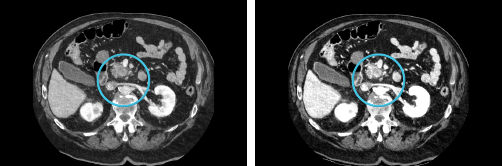

Monochromatic images

Left: 70 keV; Right: 40 keV. Monochromatic images at lower energy levels can achieve higher CNR and benefit lesion depiction and target delineation. Monochromatic images at higher energy levels have the benefits of beam hardening reduction. Monochromatic images potential benefits for radiation oncology: enhanced lesion depiction, precise target delineation, beam hardening reduction, and potential for precise target delineation and dose calculation.

Material density

Iodine color maps. The material density images (MD) provide qualitative and quantitative information regarding tissue composition and contrast media distribution, increase tissue contrast and amplify subtle differences in attenuation between normal and abnormal tissues. The material density benefits for radiation oncology: enhanced lesion detection, characterization and delineation, and potential for post-treatment tumor vitality monitoring.